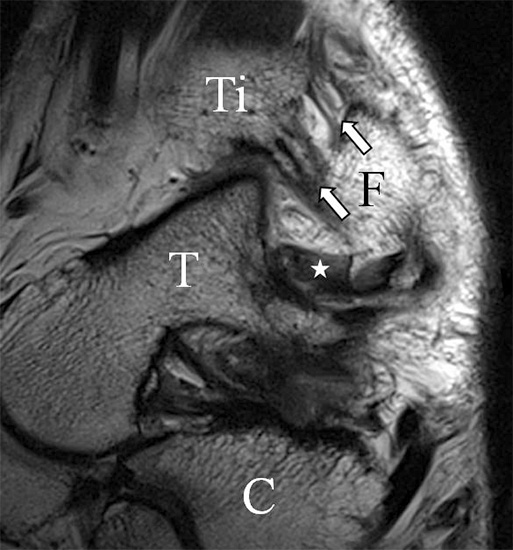

Bezogen auf die Transversalebene verläuft die Syndesmose ca. 30° schräg cranio-caudal anguliert (Abb. 15 a). Häufig lassen sich drei Hauptfaszikel differenzieren: das kürzeste superiore, das stärkste mittlere und das längste kaudale Faserbündel. Ein akzessorisches Bündel, das anteriore-inferiore, tibiofibulare Ligament (AITFL) oder auch Bassett-Ligament wird in 80-94% der Patienten nachgewiesen 8. Dies weist einen unmittelbaren Bezug zur anterolateralen Talusschulter auf (Abb. 17). In Kombination mit einer Außenbandinstabilität und konsekutivem, talarem Vorschub kann dieses zu einem Impingement an der anterolateralen Taluskante führen mit nachfolgender chondraler oder osteochondraler Läsion.

Das Ligamentum fibulotalare anterius entspricht einer bifaszikulären Struktur (Abb. 2 a) mit interponierendem fibrovaskulärem Gewebe (S. K. Sarrafian (ed). 2003). Es gibt jedoch Variationen der Ligamentanatomie. In 55% liegt das LFTA als bifaszikuläres Band (Abb. 2 a), in 9% als monofaszikuläre Bandstruktur (Abb. 2 b) und in 36% als multifaszikuläre, striäre Variante (Abb. 2 c) vor 3.

Der Ursprung des Ligamentum fibulocalcaneare liegt unmittelbar kaudal und dorsal des Ursprungs des Ligamentum fibulotalare anterius, so dass gehäuft kombinierte Verletzungen und auch ein gemeinsamer knöcherner Ausriss beobachtet werden. Nach kaudal dorsal verläuft das Band dann nach medial konvex unter die Peroneussehnen. Danach ist ein schräg deszendierender, gestreckter Verlauf bis zum calcanearen Ansatz abgrenzbar (Abb. 10). Dieser zu allen drei Standardebenen schräge Verlauf erschwert häufig die Diagnostik des LFC vor allem bei subtileren Verletzungen. Spezialprojektionen, die dem Bandverlauf orthograd folgen (entweder schräg coronar oder schräg sagittal) erleichtern auch hier die Diagnostik (Abb. 11) insbesondere nicht dislozierter Avulsionen. Assoziierte Verletzungen der Peroneussehnenloge müssen mit beurteilt werden, wobei neben Verletzungen der Sehnen und Sehnenscheiden die Beurteilung des Retinaculum peroneum superius und inferius wichtig ist. In einem Kollektiv von Patienten mit chronischen Außenbandinstabilitäten weisen 50% der Patienten eine Verletzung dieser Strukturen auf 5. Auch hier erleichtern hochauflösende Techniken die Diagnostik (Abb. 12).